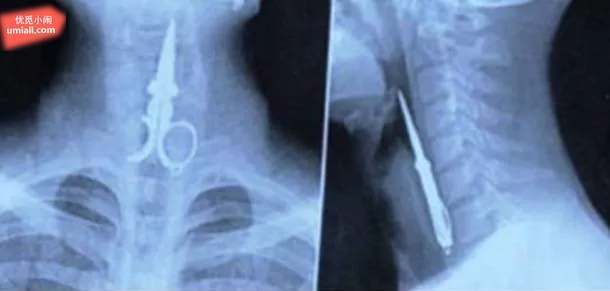

4. 他吞了一支剪刀…?